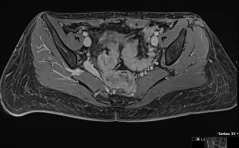

Der spezielle Fall

Retroperitoneales Ganglioneurom im kleinen Becken PDF Dokumentin - out